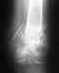

Мама, 52 года, в декабре ударила локоть, оказался перелом. Наложили гипс на 3 недели. После снятия гипса оказалось, что рука не может разогнуться в локтевом суставе и нарушена подвижность пальцев.

Была сделана электромиография, показало нарушение проводимости лучевого нерва, проводимость всего 20%. Сейчас принимает лечение нейромидином, физиопроцедуры парафин, электрофорез, ультразвук, магнитотерапия результата не дали. Лечащий врач ничего не объясняет, отмахивается, уже и не обещает восстановления подвижности руки. Суставы локтя и пальцев поражены артрозом. Какие перспективы у моей мамы в плане выздоровления, к какому врачу обратиться и что можно предпринять? Времени после травмы все больше, шансов восстановиться, боюсь, все меньше...